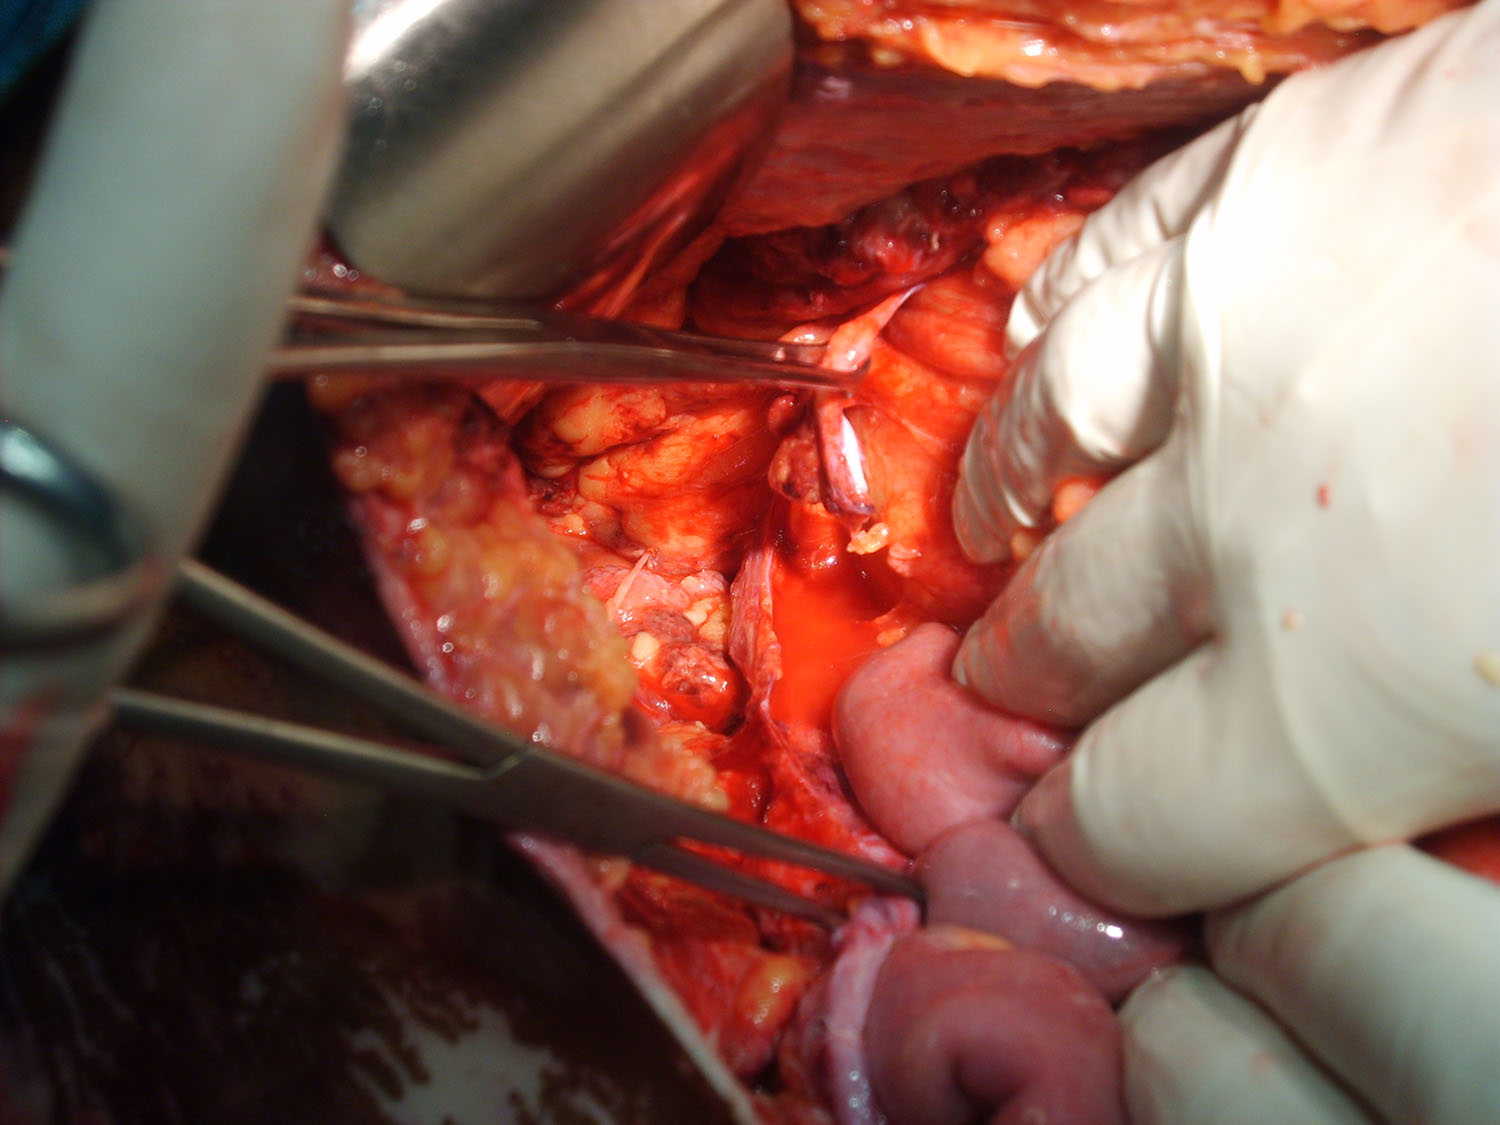

Luego de estabilizada la paciente y al cuarto día de la cirugía del abdomen abierto se lleva la paciente al quirófano. Se constata abdomen con escaso liquido serohemático y asas intestinales sin compromiso vascular por lo que se decide cerrar el abdomen. Es dificultosa la tarea de contener las asas intestinales en la cavidad abdominal debido a la ausencia de pared lateral. Se decide el decolamiento del colon derecho e izquierdo a fin de lograr un espacio para colocar la prótesis, es decir generar un espacio real con el peritoneo para introducir la malla. La sugerencia adecuada del Dr Zorraquino es imposible de realizar, la enferma presenta una retracción importante de los músculos rectos que determinan una cavidad abdominal que supera ampliamente los 900 cm². Se coloca dos mallas de proceed 30 x 30 intraperitoneal fijadas con puntos al espesos total de los remanentes musculares y sobre la misma una malla de prolene 30 x 30 fijada abajo al pubis y a ambas crestas ilíacas y por arriba al plano aponeurótico de los rectos y Oblicuo mayor. Se deja piel y celular abierto. Vuelve a Cuidados Intensivos.

Posteriormente hemos colocado una prótesis de PPL para dar consistencia a la plastia, incluso tumbando al paciente tras unir los extremos musculares. Se trata de crear una nueva aponeurosis sobre los músculos (Carbonell-Bonafé) y , por tanto, debemos anclarla al marco óseo del abdomen: xifoides-pubis, arcos costales-crestas iliacas. Dejando los laterales por debajo de la aponeurosis del Oblicuo Mayor (OM) anclando el extremo de esta aponeurosis sobre la malla; así conseguimos que la compliance del OM absorba las diferencias de presión intra-abdominal.

Estimado Dr Reyes, aprecio tus comentarios, nosotros no disponemos de mallas biológicas, que si creo hubiesen sido de utilidad en este caso.Con respecto a colocar malla de polipropileno sobre la proceed, fué para tratar de darle más contención al contenido abdominal, por eso esa prótesis la fijamos al pubis y a las crestas ilíacas que estaban totalmente a la vista, según mostramos en algunas fotos.